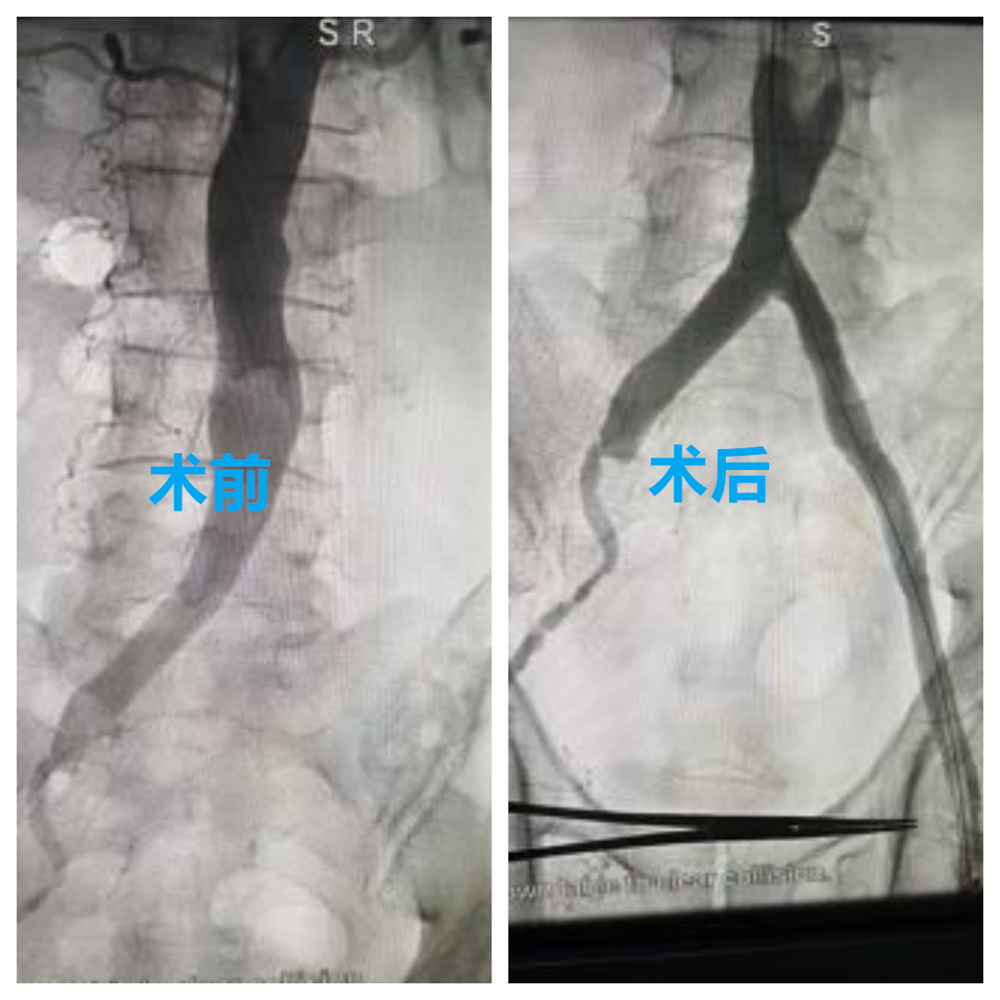

▲双下肢动脉狭窄闭塞术前术后对比

在手术团队的精准操作下,患者顺利接受了左髂动脉支架置入术、左股动脉支架置入术、左股动脉内膜剥脱术、左股动脉血管成形术、左下肢动脉球囊扩张成形术等一系列手术治疗。

术后,科室采用壮医药熨、壮医耳穴等壮医外治疗法结合壮药内服进行综合康复治疗,帮助调理气血、温通经络、增强免疫。经过两周的治疗,患者下肢血流明显改善,踝肱指数(ABI)由术前0.2提升至0.8,行走能力较前明显提升,跛行症状减轻,日常活动逐步恢复,并计划后续接受另一侧肢体治疗。

▲髂动脉股动脉术前术后对比